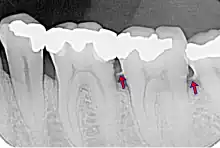

- le tartre supra-gingival : c'est celui qu'on peut voir à l'œil nu. Il est généralement de couleur blanchâtre ;

- le tartre sous-gingival : c'est le tartre qui s'est déposé sur la racine de la dent, à l'abri de la gencive, au niveau des poches parodontales. Il est souvent beaucoup plus foncé. Ce tartre est le plus dommageable : les bactéries sont protégées à l'intérieur de la poche, et progressivement la flore aérobie se transforme en flore anaérobie, plus pathogène. Par ailleurs, comme on ne le voit pas, on ne s'en rend pas compte.